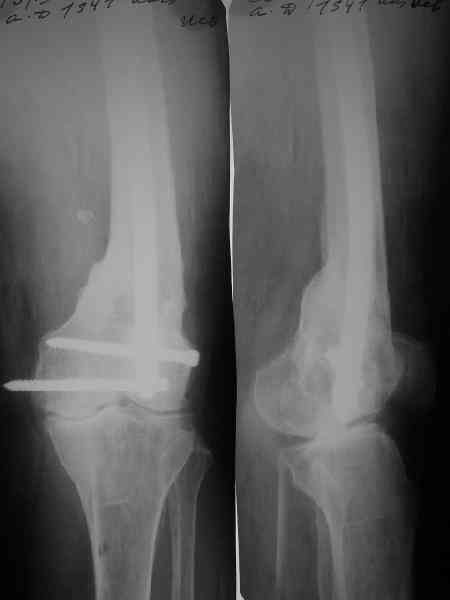

Пример подобного ложного сустава в приложении.

На сегодня есть имплантаты с куда более продвинутой дистальной фиксацией.